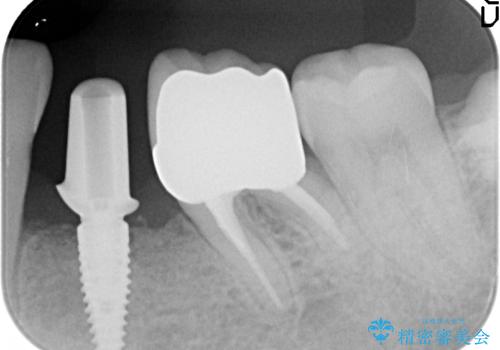

歯列矯正は御希望されなかったため左下4、5番目の歯を抜歯し、インプラントによる欠損補綴を行いました。

ストローマンについて

当院では主にストローマンという種類のインプラントを治療に用いています。

ストローマンは世界的にもNo1のシェアを誇り、骨との適合にも優れたインプラントです。

カスタムアバットメントについて

カスタムアバットメントは患者様それぞれの歯茎に合わせて製作されたオーダーメイドのアバットメントです。

既製のアバットメントに比べ適合がよく、高い清掃性を誇ります。